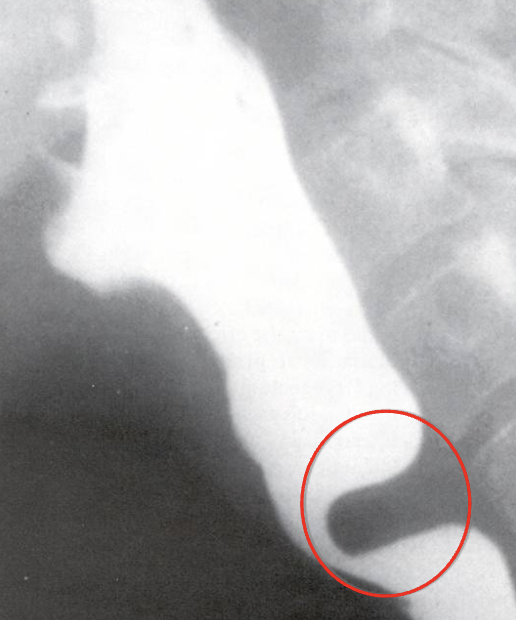

<p>What esophageal disorder is this?</p>

What esophageal disorder is this?

Web at PES